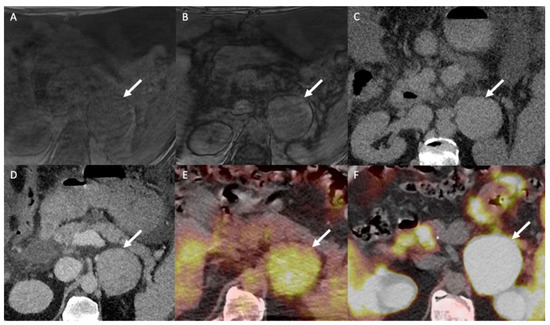

- Jamali, S.; Michoux, N.; Coche, E.; Dragean, C.A. Virtual unenhanced phase with spectral dual-energy CT: Is it an alternative to conventional true unenhanced phase for abdominal tissues? Diagn. Interv. Imaging 2019, 100, 503–511. [Google Scholar] [CrossRef]

- Nagayama, Y.; Inoue, T.; Oda, S.; Tanoue, S.; Nakaura, T.; Ikeda, O.; Yamashita, Y. Adrenal Adenomas versus Metastases: Diagnostic Performance of Dual-Energy Spectral CT Virtual Noncontrast Imaging and Iodine Maps. Radiology 2020, 296, 324–332. [Google Scholar] [CrossRef]

- Lestra, T.; Mule, S.; Millet, I.; Carsin-Vu, A.; Taourel, P.; Hoeffel, C. Applications of dual energy computed tomography in abdominal imaging. Diagn. Interv. Imaging 2016, 97, 593–603. [Google Scholar] [CrossRef]

- Connolly, M.J.; McInnes, M.D.F.; El-Khodary, M.; McGrath, T.A.; Schieda, N. Diagnostic accuracy of virtual non-contrast enhanced dual-energy CT for diagnosis of adrenal adenoma: A systematic review and meta-analysis. Eur. Radiol. 2017, 27, 4324–4335. [Google Scholar] [CrossRef] [PubMed]